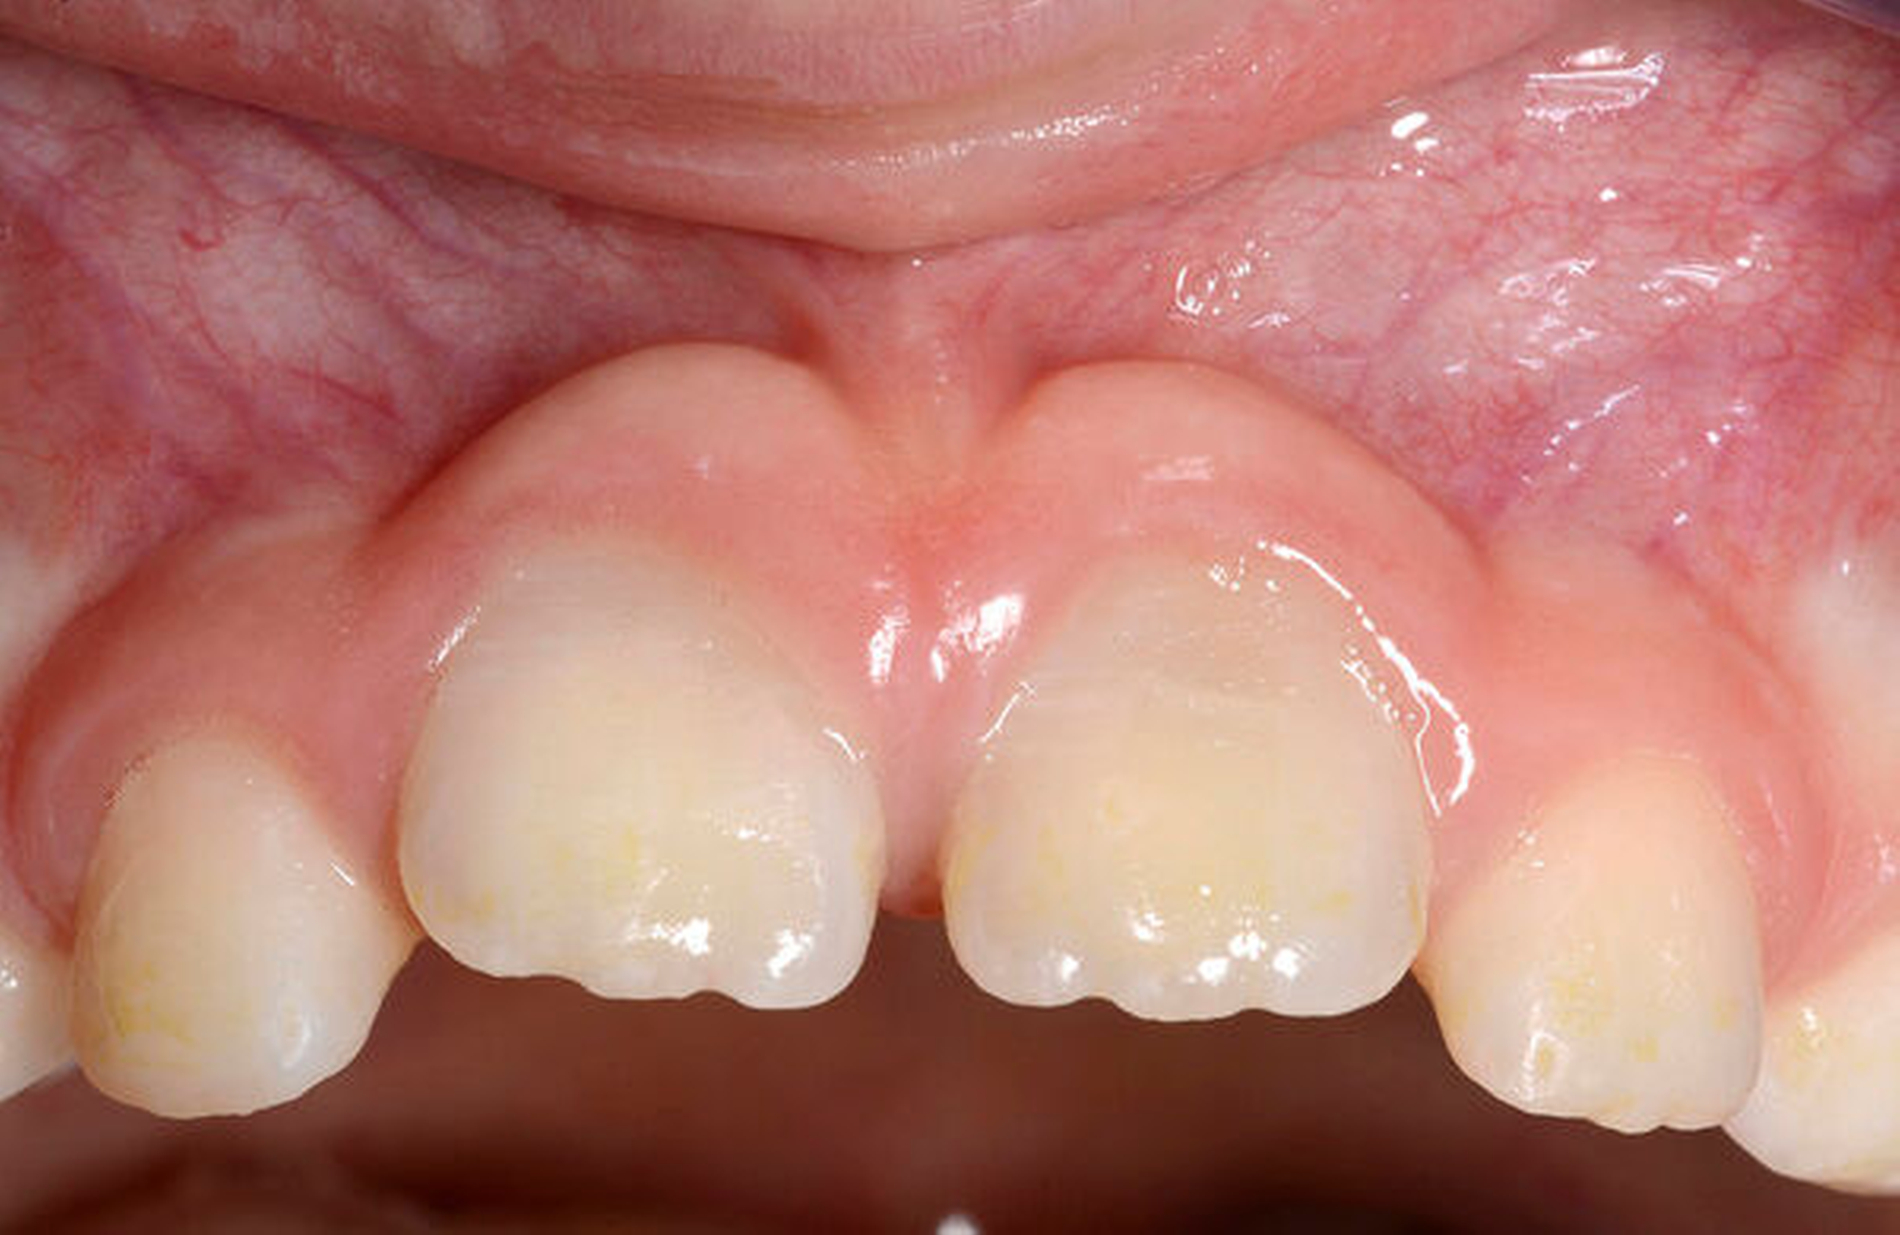

Die Häufigkeit für den Frontzahnverlust beträgt drei bis vier Prozent. Die Altersgipfel liegen zwischen dem achten und dem neunten sowie vom zwölften bis zum 14. Lebensjahr. Betroffene Zähne sind der mittlere und der seitliche Schneidezahn im Oberkiefer. Es besteht eine Korrelation der Häufigkeit zu den Zahnstellungsanomalien der vergrößerten sagittalen Schneidekantenstufe, dem schmalen Deckbiss mit protrudierten seitlichen Schneidezähnen und progen stehenden Einzelzähnen. Obwohl bei Avulsion die sofortige Reimplantation zum Erhalt des Zahnes führen kann, sind häufig Ankylosen des Parodonts und Wurzelresorptionen mit begrenzter Erhaltungswürdigkeit die Folgen. Eine fehlende Sensibilität, ein hoher Klopfschall und der röntgenologische Resorptionsnachweis sind diagnostische Anzeichen dafür.

Traumatischer Verlust eines oberen Schneidezahns im Alter zwischen acht und zwölf Jahren ohne und mit Reimplantation

Erfolglose Reimplantation (Wurzelresorption und Lockerung)

Fehlender Abschluss des Wurzelwachstums, weites Foramen apikale und Avitalität. Eine endodontische Aufbereitung ist aufgrund des divergierenden Wurzelkanals schwierig.